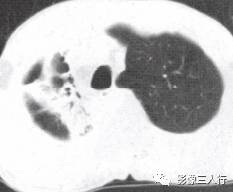

由于实变的肺组织与含气的支气管相衬托,在实变区中可见透明的支气管影即空气 支气管征,临床常见于大叶性肺炎的实变期,包括红色肝样变及灰色肝样变期,表现为密度均匀的致密影内可见透明的支气管影(图1)。这一征象被认为是肺泡炎性病变的有力证据。